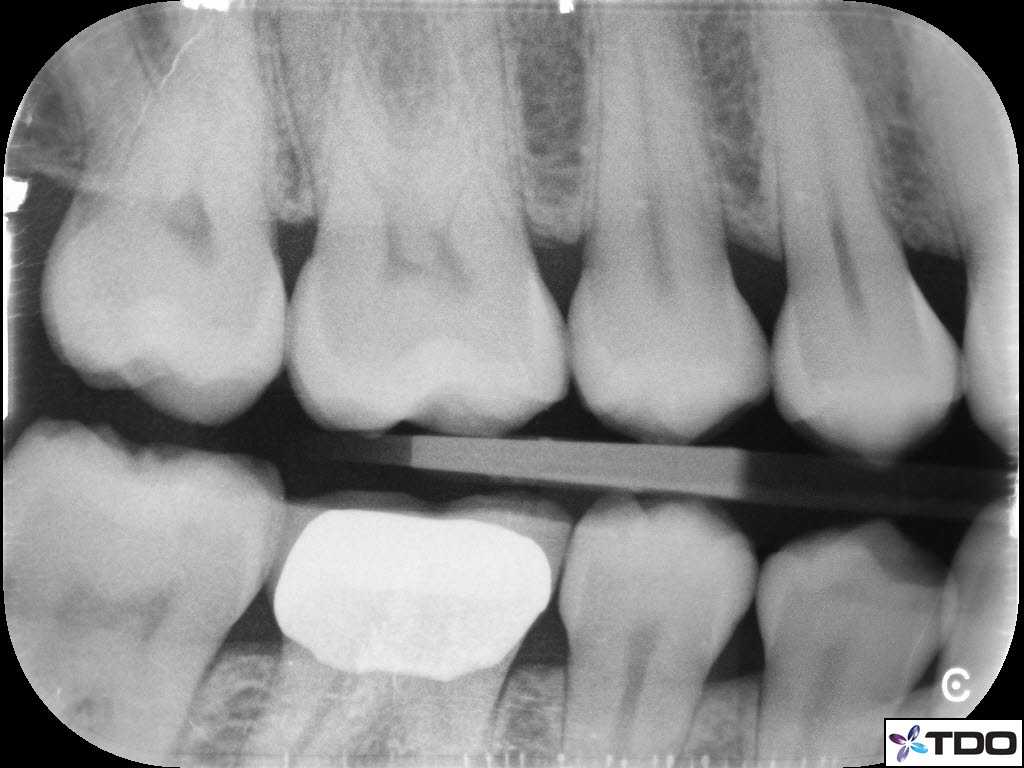

In the hierarchy of dentin conservation the existing restorative has the lowest priority and it quite frankly gets in the way of our access to the root canal system. But, after practicing directed dentin conservation for a while, you sometimes get lucky. The patient is 40yo. She was symptomatic at the time of treatment and interestingly the mesiobuccal canal was partially vital while the mesiolingual, distobuccal and distolingual canals were partially necrotic. She was asymptomatic at the completion visit as well as at the follow-up appointments.